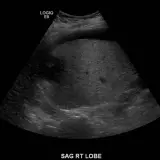

Over 2,100 interactive radiology cases, curated by radiologists for your level of training. Scroll, window, and view cases full screen — just like on PACS. Click linked findings in each writeup to jump straight to them on the image. Cases include sample reports, a focused discussion section, original illustrations, and videos.

完全交互式病例,配备您在 PACS 上期待的各项工具——滚动、调窗、缩放、平移、测量、ROI 和全屏模式。

丰富的标注直接在病例图像上突出关键发现。点击病例讲解中的关联发现,即可跳转至其在扫描上的精确位置。